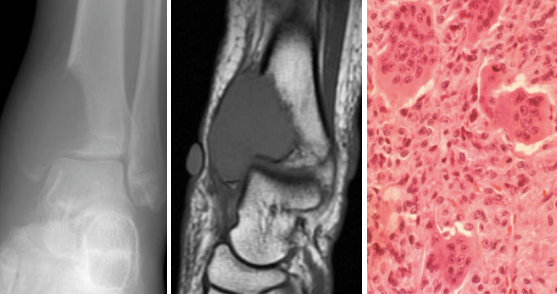

What is seen on imaging a GCT?

Xrays

MRI

Describe the histology of GCT?